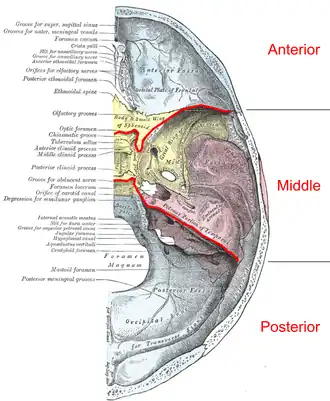

Base of skull. Superior view. Boundaries of the cranial fossae drawn as red lines. | |